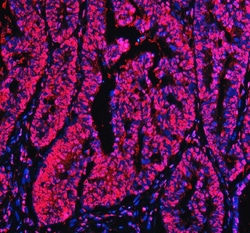

Reconstitute with 0.2 mL of distilled water to yield a concentration of 500 μg/mL. Positive Control - WB: human LNCAP whole cell, human Hela whole cell, human 293T whole cell, human HepG2 whole cell, human Jurkat whole cell, human K562 whole cell, human A549 whole cell, human A431 whole cell. IHC: human bladder cancer tissue, human bladder cancer tissue, human colon adenocarcinoma tissue, human colon adenocarcinoma tissue, human glioblastoma tissue, human glioblastoma tissue, human liver cancer tissue, human liver cancer tissue, human lung adenocarcinoma tissue, human lung adenocarcinoma tissue, human pancreas ductal adenocarcinoma tissue, human pancreas ductal adenocarcinoma tissue, human testicular seminoma tissue, human testicular seminoma tissue. ICC/IF: U2OS cell. Flow: A431 cell. Store at -20°C for one year from date of receipt. After reconstitution, at 4°C for one month. It can also be aliquotted and stored frozen at -20°C for six months. Avoid repeated freeze-thaw cycles.

| Flow Cytometry, Immunohistochemistry (Paraffin), Western Blot, Immunocytochemistry | |